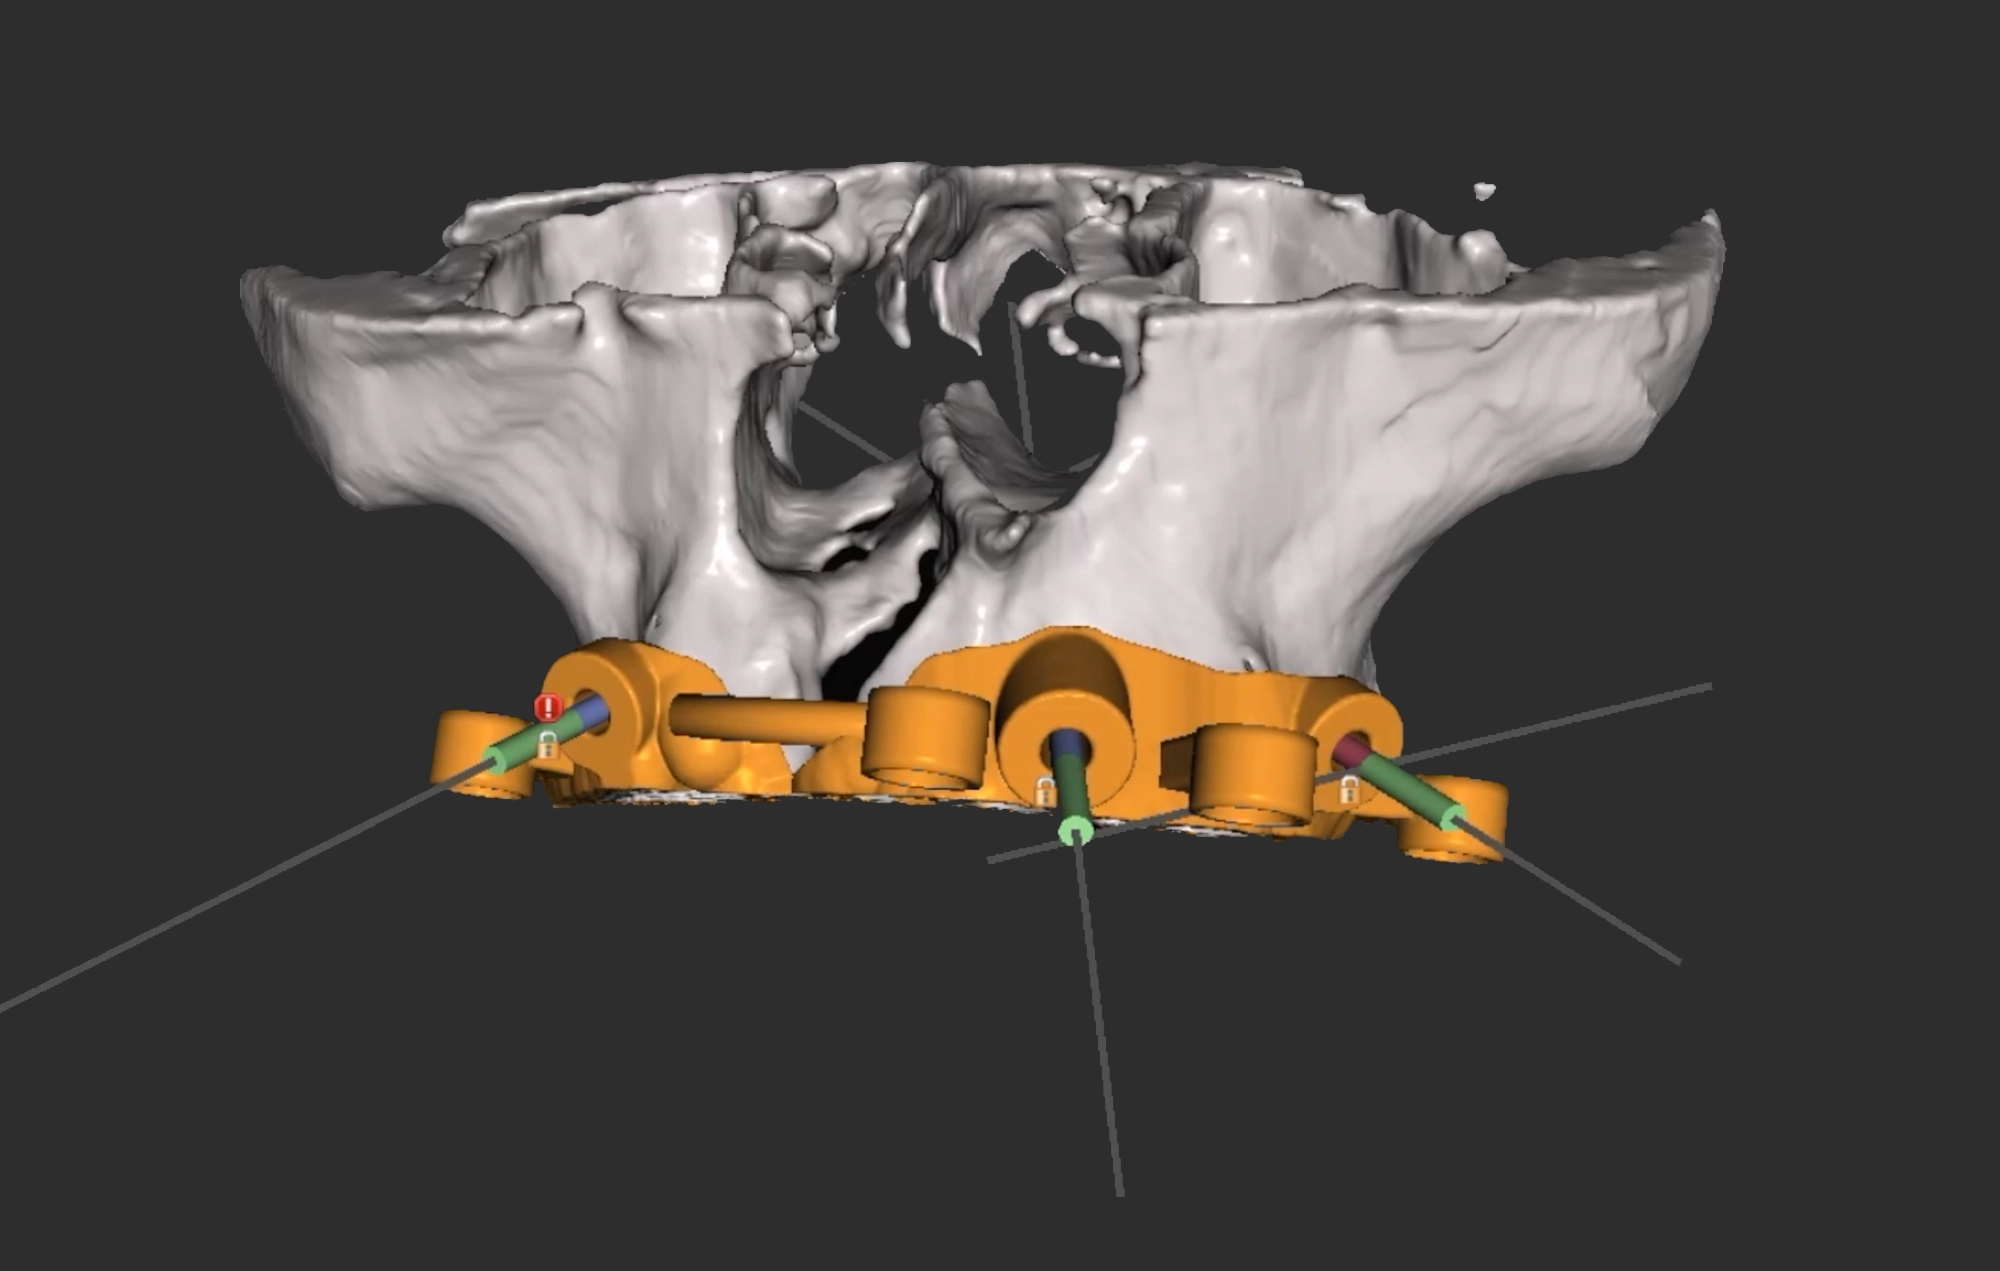

• Implantología: La cirugía guiada nos permite colocar implantes dentales incluso en los casos más complejos con resultados asombrosos.

Guías Quirúrgicas

Un elemento protésico usado en odontología por especialistas en implantología para direccionar de manera más exacta y correcta en la posición y colocación del implante.

Proceso Digital

Con software 3D de punta, especializado en modelos y proyecciones.